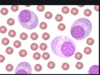

features of eosinophils

- 2 lobes (bilobed nucleus)

- cytolasm stains bright red and granular

why is the cytoplasm of an eosinophil bright red and granuklar

- Full of chemical mediators- Histamine, heparin and prostaglandins

- E.g. Release during hypersensitivity reactions and parasitic infections